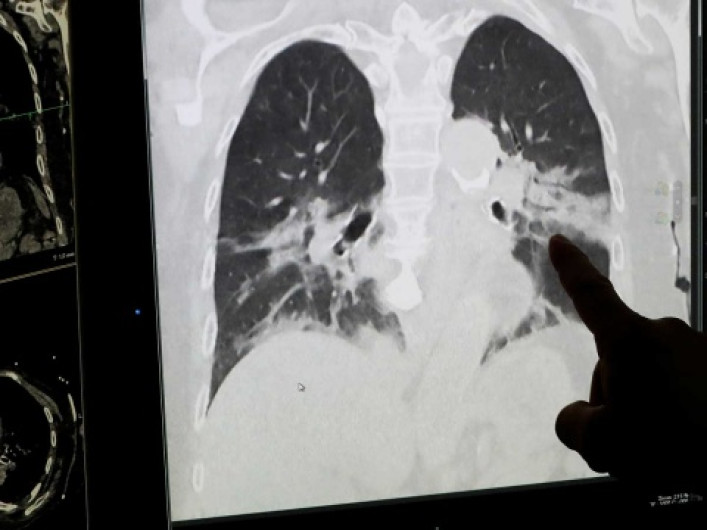

De acuerdo al director general de la Organización Mundial de la Salud (OMS), Tedros Adhanom Ghebreyesus, el mundo está lejos de someter al nuevo coronavirus.

Esta pandemia ha causado hasta ahora cerca de 180 mil muertos a nivel mundial.